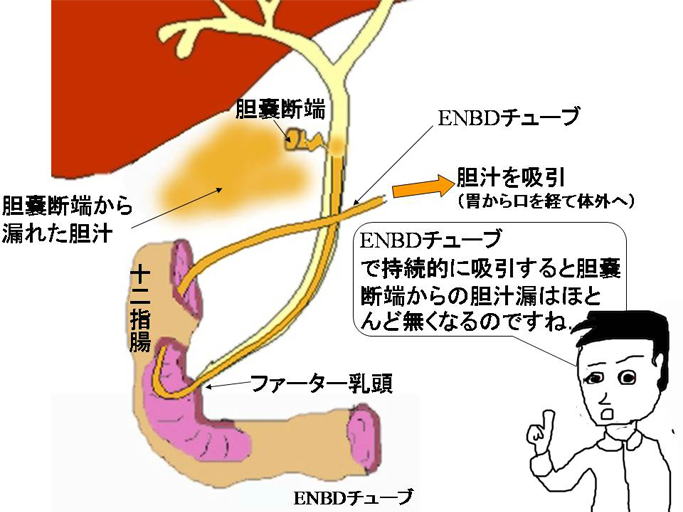

疾患での役割 [ ] 胆石症 [ ] 最大25%の人間が、、、およびで構成されたを持つ。 急性胆のう炎では、胆のうが浮腫などにより肥大しますが、慢性胆のう炎では胆のう壁が分厚くなり、胆のう自体のサイズは萎縮していきます。 写らない場合でも、胆嚢を映し出す造影剤があって、それを経口的、あるいは経静脈的に与えることにより胆嚢を映したり、内視鏡的逆行性胆管造影法によって、中にある石をみつけます。